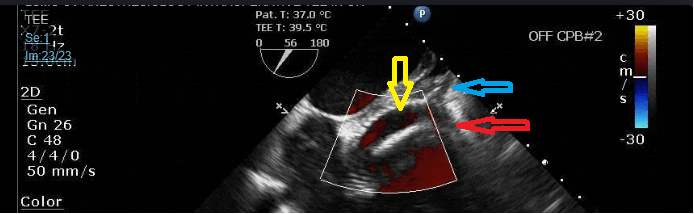

Yep, this procedure is called a Cabrol (type B in the diagram below). It's used sometimes when the aneurysm is so big or if there's some abnormality in the coronaries that prevents the normal "coronary button" implantation technique used in Bentalls. The yellow arrow is pointing to the Dacron graft that is end-to-end anastomosed to a remnant of the left main. If you look close enough at the ME AV SAX, you can even see the division into the LAD (red arrow) and Cx (blue arrow)